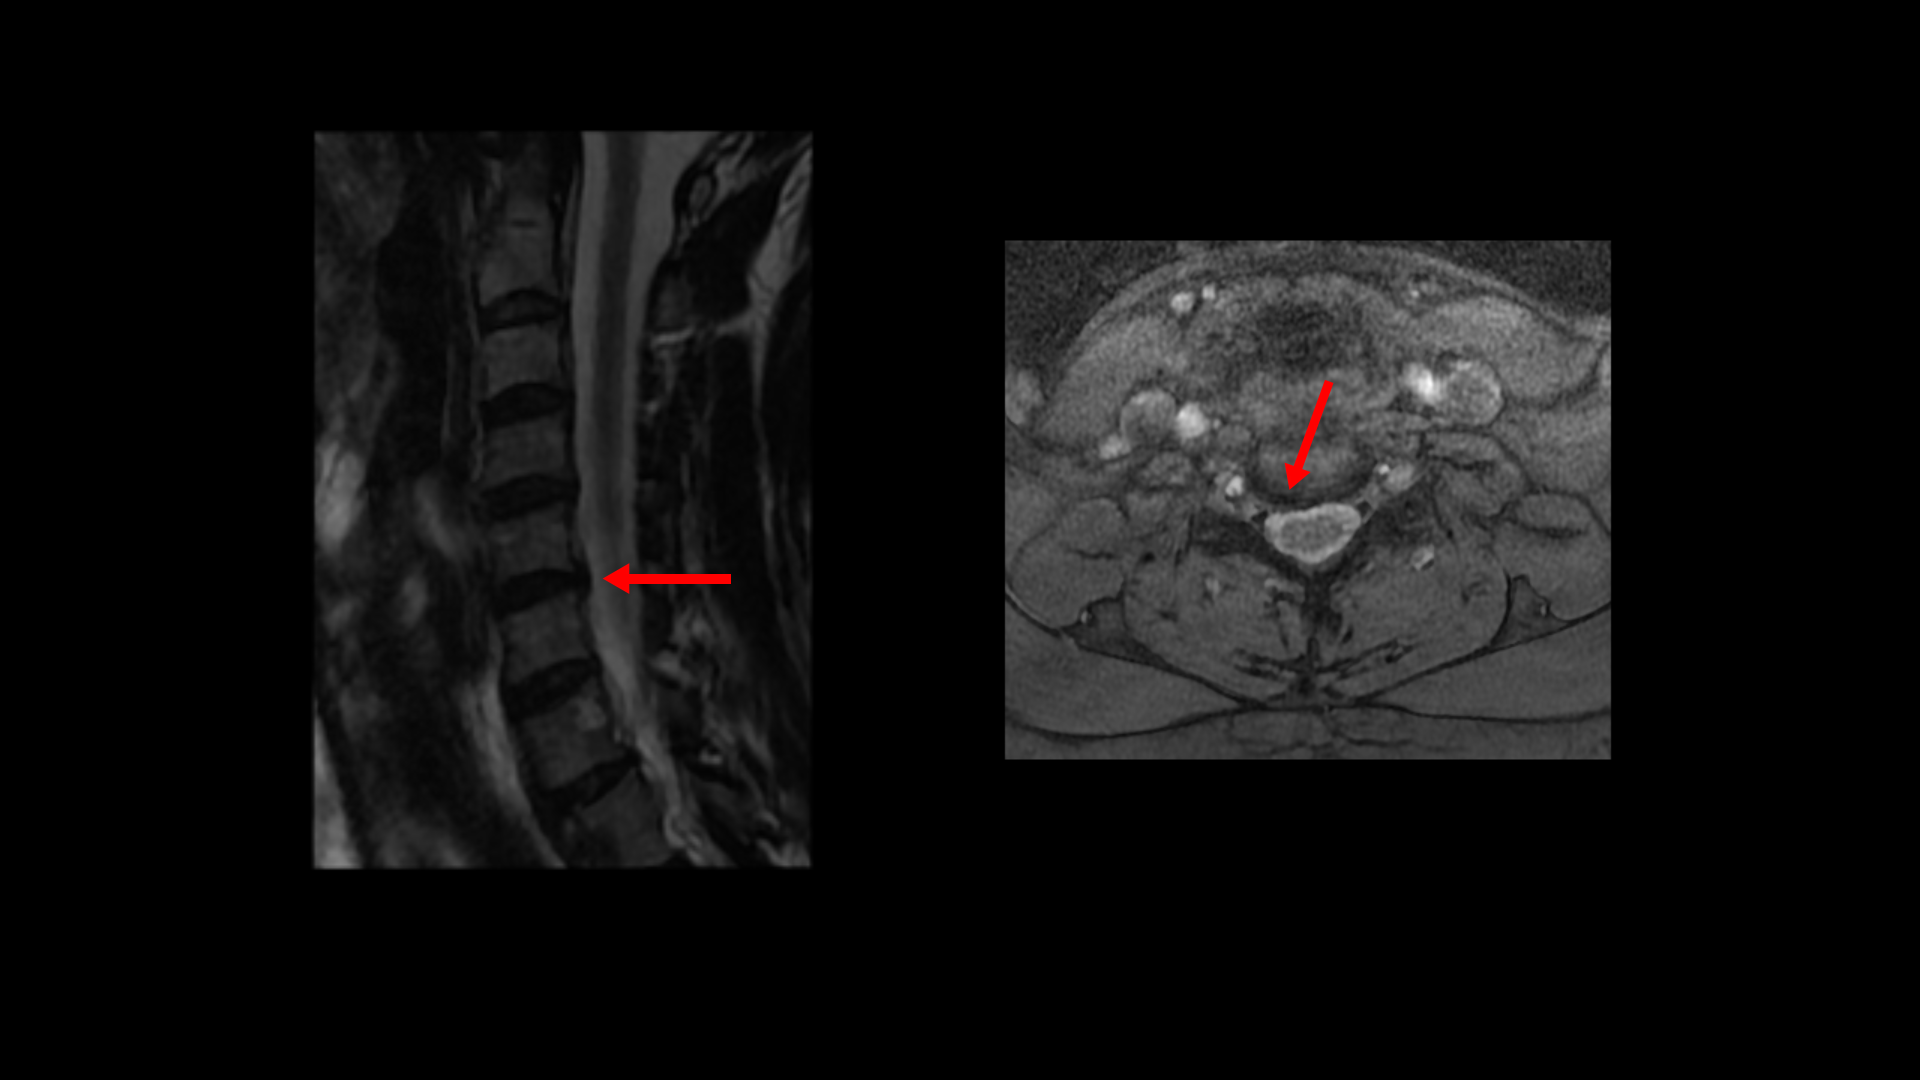

일반적으로 환자분들이 어지럽고 두통도 있고 하면 보통 이비인후과나 신경과에 많이들 가시는데, 목 근육이 뭉쳐서 아픈 사람들은 당연히 이비인후과에서는 이상이 없다는 얘기를 듣고 또 신경과에서도 아무 이상이 없다고 듣거나 혹은 후두신경통을 진단받는 경우가 많습니다. 또 만성적으로 목 통증, 어깨통증이 있기 때문에 정형외과나 통증의학과, 한의원 등에 가면 근막통증증후군이나 거북목증후군, 일자목증후군 진단을 받는 경우도 많습니다. 게다가 이렇게 목이 아픈 환자분들은 척추병원에 가서 MRI를 찍어보면 이 환자분처럼 40세가 넘은 분들은 퇴행성 디스크가 보이는 경우가 매우 많습니다.

이 환자분은 이렇게 목디스크가 보이기 때문에

척추병원에서 목디스크 때문이다라는 얘기를 듣고 신경 주사를 여러 번 맞게 됩니다. 그러나 이분 증상들을 자세히 들여다보면 목디스크 증상이 아닙니다. 목디스크 때문에 아픈 게 아니기 때문에 목디스크를 계속 치료해봐야 좋아지지 않는 겁니다.